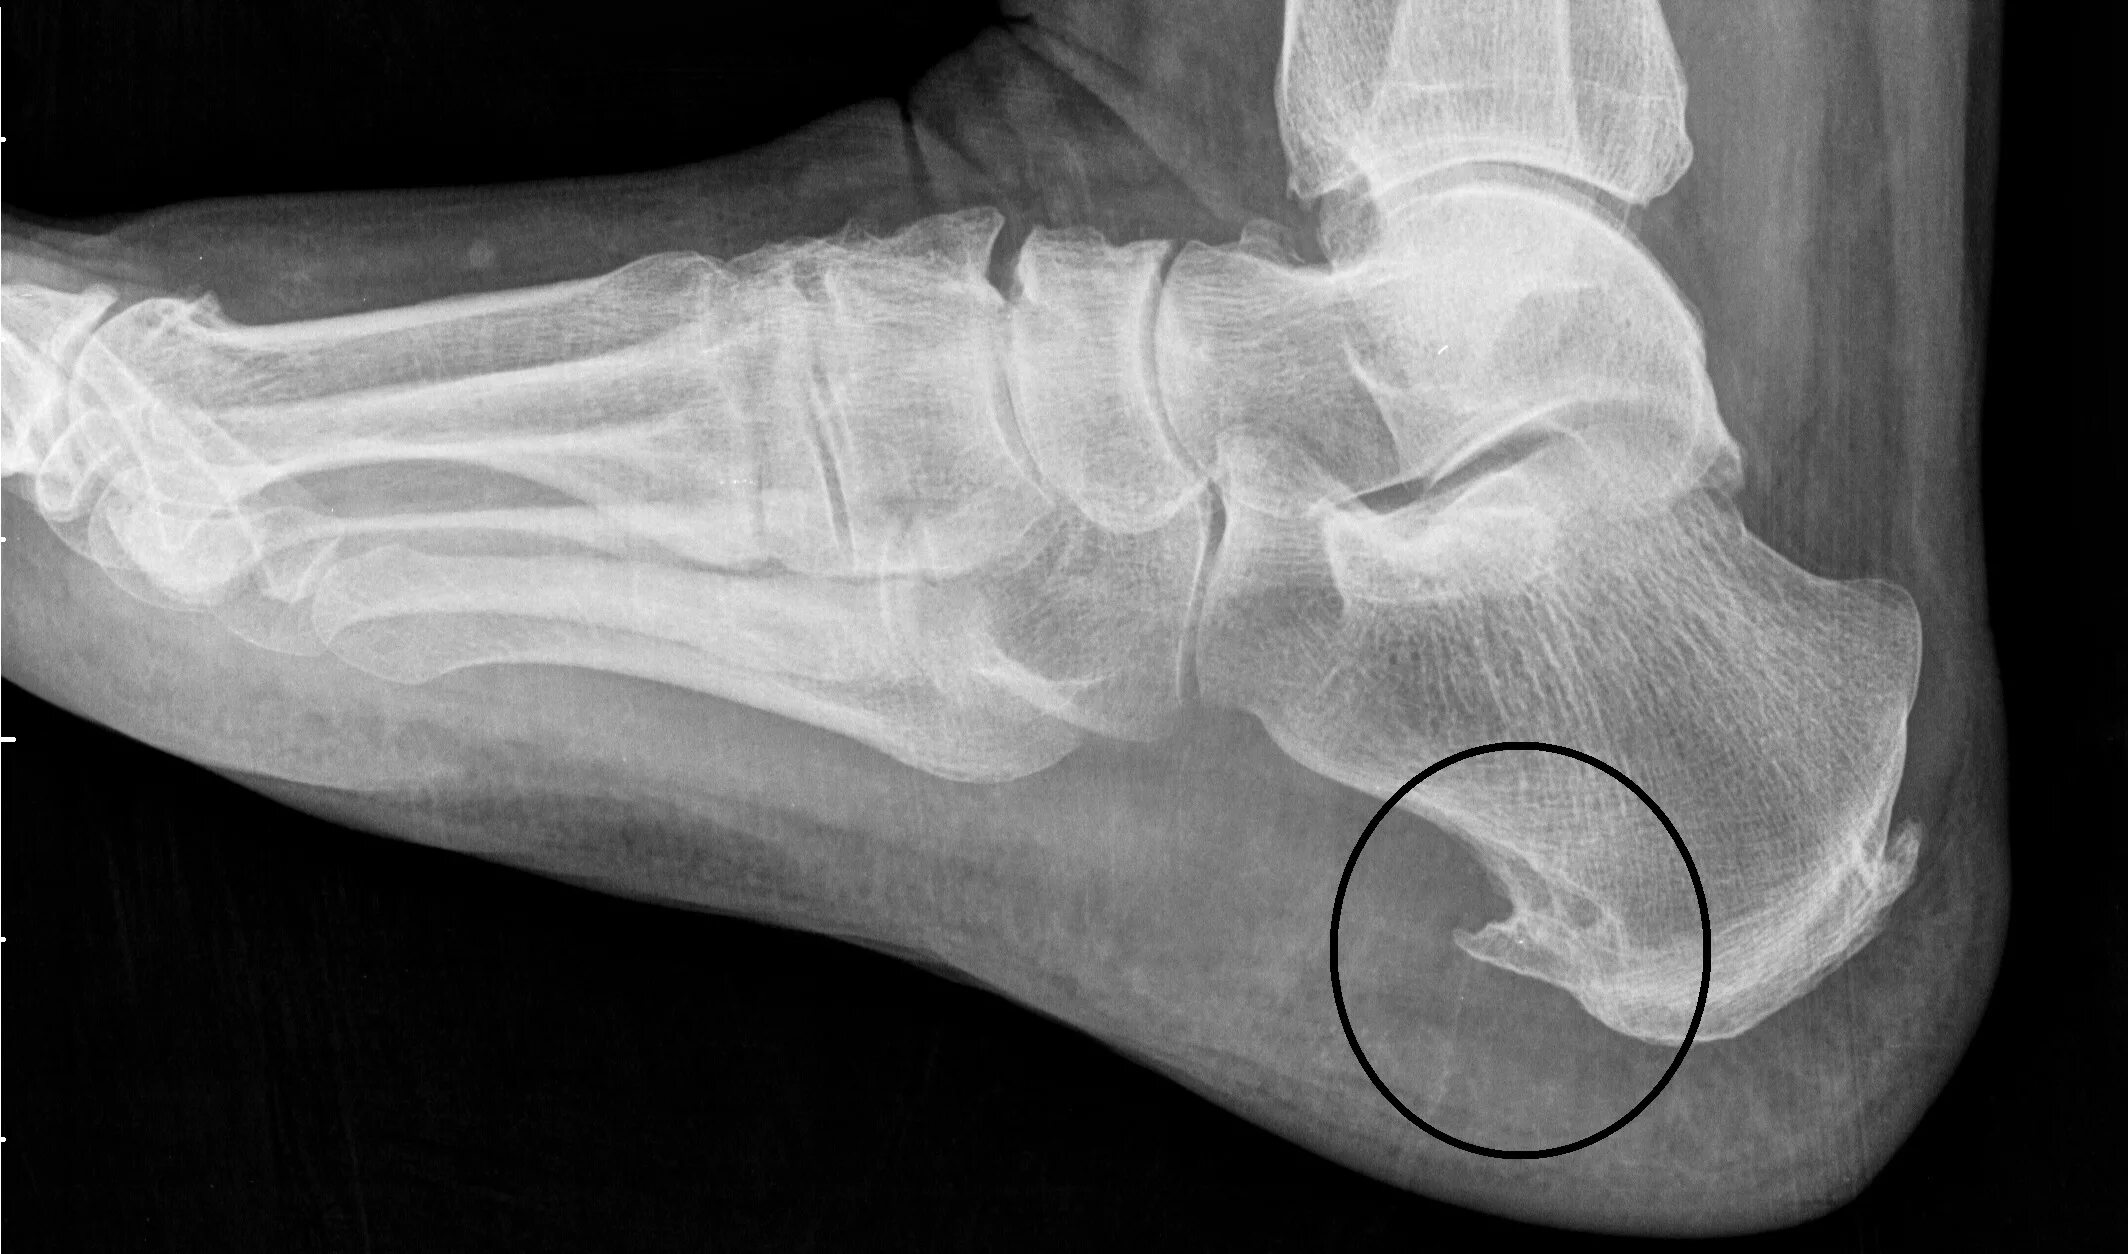

Пяточный фасцит